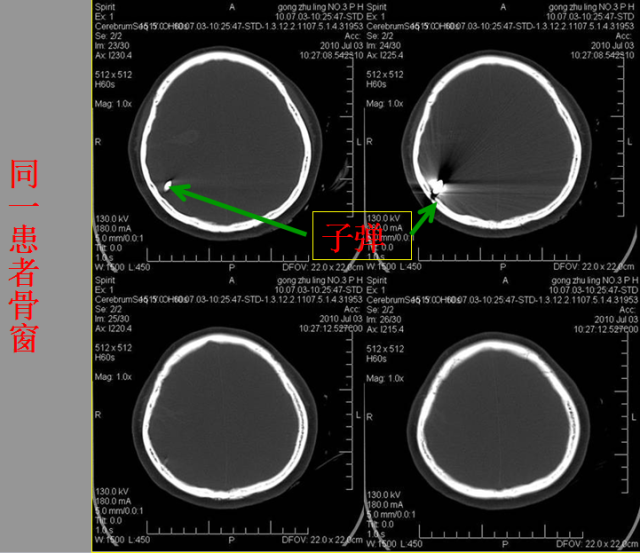

急性颅脑损伤篇

急胸症篇